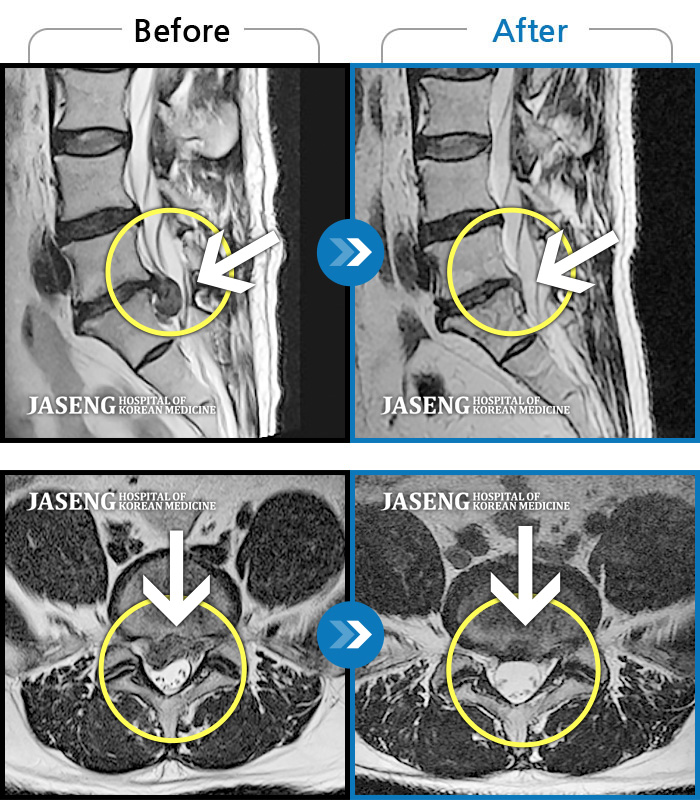

허리디스크

일산 · 김태용 원장

허리와 우측다리가 심하게 저렸다.

촬영시기

2020.05.07 ~ 2020.12.29

2021.02.26